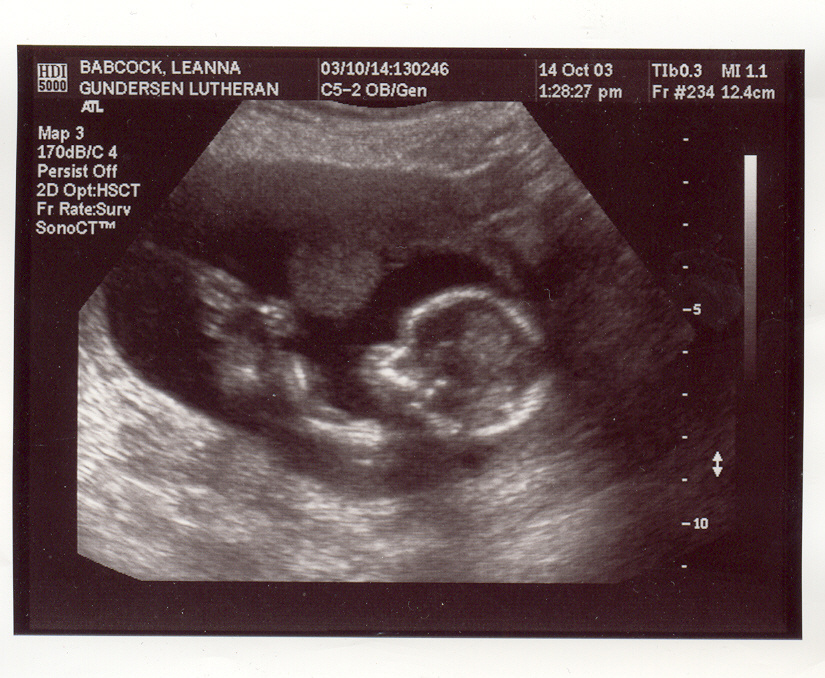

This is my new baby page. I am due at the end of March/start of April, 2004. Here are my first ultrasound pix. They may take a few minutes to load, so be patient. These ultrasound pix were taken Oct. 14th, 2003. We were unable to find out the sex of the baby because it was too early in my pregnancy and also the baby's umbilical cord was between it's legs, and whenever we tried to see what was down there that was blocking our view, and also the baby would put it's hands in the way. I go in for another ultrasound on Nov. 11th. I will post more pix up after then. The baby seems to be healthy at this point and Aidan and I are very excited and preparing for our first child with joy in our hearts! :)